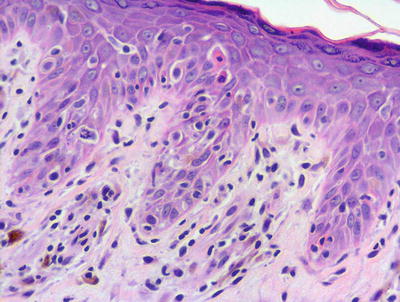

Drug eruptions manifest with many histologic patterns, one of which is a histologic mimic of lichen planus. In these cases, the epidermis may be slightly acanthotic with variable hyperkeratosis. Parakeratosis is present in some cases. The papillary dermis demonstrates a band-like inflammatory infiltrate that invades the lower portion of the epidermis, resulting in basal vacuolization, dying keratinocytes, and even small subepidermal blister formation (Figs. 4.13 and 4.14). In most cases, eosinophils and/or plasma cells will be present in addition to lymphocytes and histiocytes [1]. Their presence helps to make this distinction, along with a good clinical history. Further more, lichenoid drug eruptions often display involvement of the deeper dermis, which is not usually seen in lichen planus. Another differential diagnosis is an arthropod bite reaction. Arthropod bite reactions have a different clinical presentation from a lichenoid drug eruption . The presence of a punctum, dermal hemorrhage, and frequent eosinophils extending between reticular dermal collagen bundles all favor an insect bite reaction over a lichenoid drug eruption.

Lichenoid drug eruption demonstrates a band-like infiltrate of lymphocytes in the papillary dermis with focal exocytosis into the epidermis. Hypergranulosis and rare dying keratinocytes may be present

Fig. 4.14

Hypergranulosis , a band-like lymphocytic infiltrate and pigment-laden macrophages are present in lichenoid drug eruption